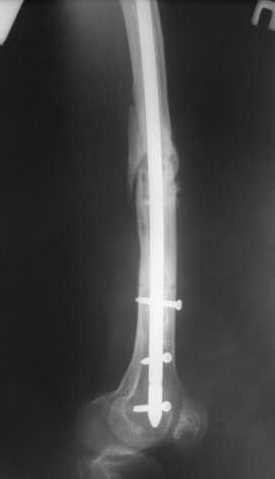

Пациенту М., 30-ти лет, 1,5 года назад в одной из московских больниц был выполнен остеосинтез бедренной кости штифтом UFN (диаметр штифта 9 мм).

К нам больной поступил с признаками ложного сустава бедренной кости, перелома

штифта и дистального блокирующего винта (images 1,2,3).

27 марта выполнено удаление блокирующих винтов (сломанный винт пришлось высверливать цапфен-бором), сломанного штифта (дистальный фрагмент удален через канал, образованный разверткой из коленного сустава - image 4),

рассверливание костно-мозгового канала, реостеосинтез штифтом UFN (при проведении штифта в дистальном отломке мы использовали поляризующий винт, диаметр штифта 10 мм). После операции в связи гемартрозом дважды (на 1 и 3 сутки) выполняли пункцию коленного сустава. Сейчас признаков скопления жидкости в полости сустава нет. Послеоперационные рентгенограммы - images 5, 6, 7.